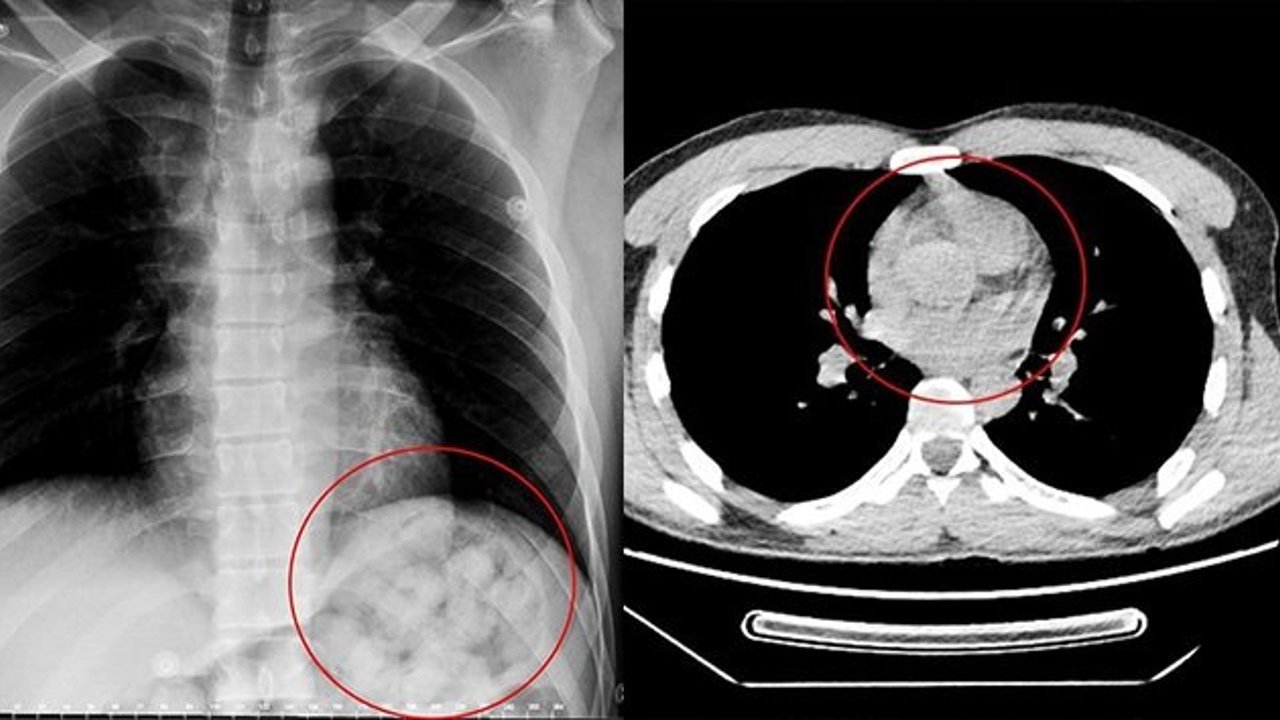

Edinilen bilgiye göre, 5 gün önce Van'dan otobüsle Ankara'ya gelen O. Zahed Ahmed Narziveh rahatsızlanınca hastaneye kaldırıldı. Ankara Şehir Hastanesine getirilen şahsın röntgen görüntüleri gerçeği ortaya çıkardı. Şahsın midesinde 890 gram ağırlığında 2'si patlamış halde 72 kapsül olduğu ve kapsüllerin patlaması ile fenalaştığı belirlendi. Mahkeme kararına istinaden ameliyata alınarak midesindeki metamfetamin kapsülleri çıkartılan zanlı, Ankara Emniyet Müdürlüğüne bağlı Narkotik Suçlarla Mücadele ekiplerince hastanedeki 5 günlük tedavisinin ardından adliyeye sevk edildi.